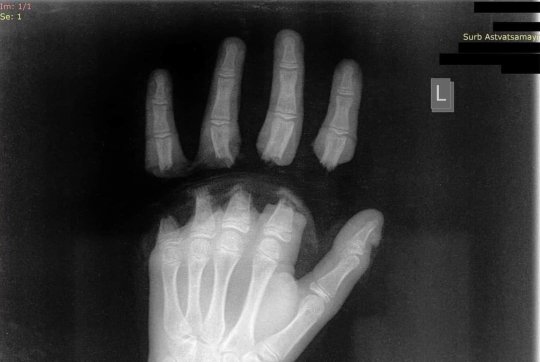

ԲԿ է ընդունվել 12-ամյա երեխա՝ ձեռքի 4 մատներն անդամահատված. դեպքը տեղի է ունեցել շան հետ խաղալիս